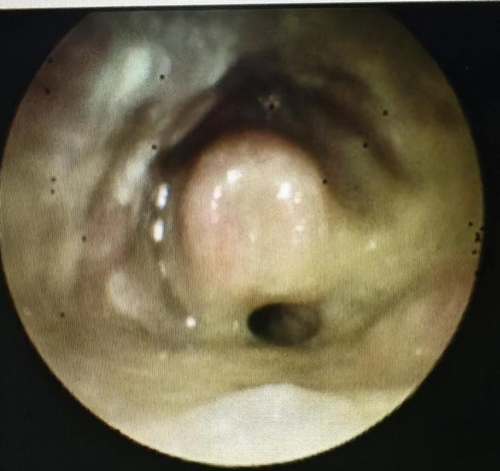

患者电子喉镜检查图(舌根、下咽、喉部大面积肿胀、溃疡合并脓性分泌物附着)

据了解,老人饮用热水后便感到咽喉剧痛,随后出现呕吐、声音嘶哑等症状,家人紧急将其送至医院。经电子喉镜检查,医生发现其咽喉部已出现广泛溃疡,伴有大量脓性分泌物;会厌肿胀明显,气道受压严重,随时可能发生窒息。加之患者高龄,合并高血压、糖尿病等基础疾病,风险极大。